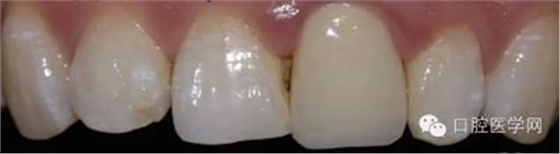

5、3MU200樹脂粘接劑粘固全瓷冠術(shù)后照

6、術(shù)后一周照,牙齦恢復(fù)良好